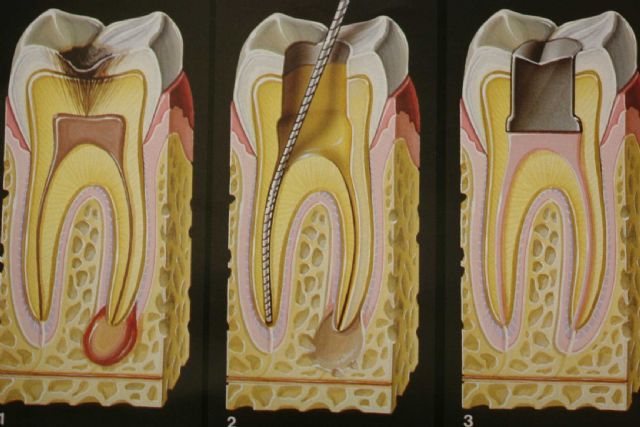

Endodonti (Kanal Tedavisi)

Enfekte olmuş dişleri kurtaran kanal tedavisi. Ağrısız ve konforlu tedavi süreci.